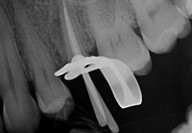

► Scouting Glide Path e Preflaring

Galleria fotografica